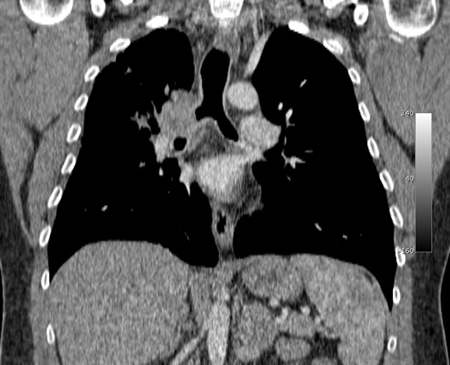

Злокачественная эндобронхиальная обструкция на мультидетекторной КТ: корональная реконструкция, демонстрирующая злокачественную обструкцию правого главного бронха

Из коллекций Хосе Фернандо Сантакруза, дипломированного врача, члена Американской коллегии специалистов в области торакальной медицины, DAABIP, и Эрика Фолка, дипломированного врача, магистра наук; используется с разрешения